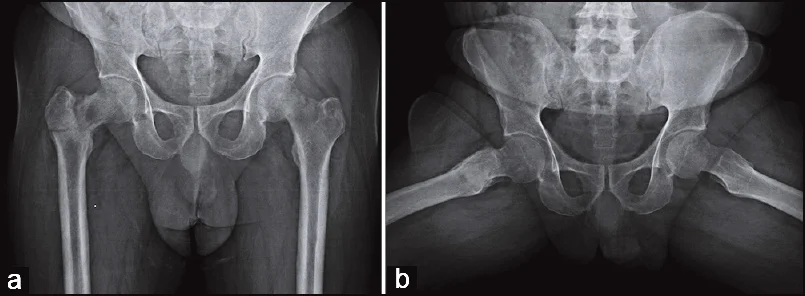

- x-ray AP and lateral view of forearm, show a displaced fracture in both radius and ulnar shaft with elbow dislocation

- x-ray of male pelvis and proximal femur, AP view, mature bone fracture in greater trochanter in right side, fracture in neck of femur on left side